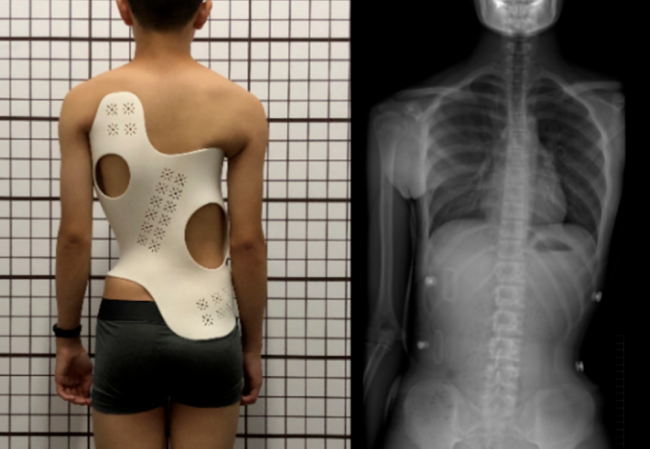

• 醫(yī)療器械